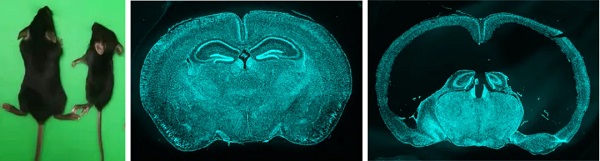

通过将Sspo-Cre和Sspo-CreER与DTA小鼠进行杂交,研究者们成功去除了子代小鼠的部分或者绝大部分SCO细胞。研究团队发现,当小鼠缺失SCO后,它们体型矮小,行动障碍,总体存活率很差。进一步发现,SCO缺陷小鼠的脑明显膨出,皮层很薄,局部皮层坍塌凹陷。脑切片显示,小鼠的脑室明显扩张,出现严重的大脑发育畸形。这些结果揭示SCO对大脑的生长发育是非常重要的,它是大脑生长发育不可或缺的一个重要器官(见图)。